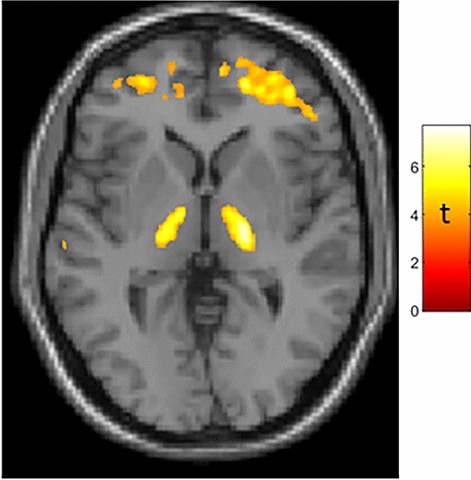

In the combined group of women and men (who did not differ in chronologic age, brain age, difference between brain and chronologic age, nor BMI; subject demographics are presented in Supplementary Table 1) SPM analysis showed greater BPnd in association with greater age (both chronologic and brain) in bilateral thalamus (Fig. 1), in accord with prior TSPO PET studies10,11,12. We did not find age-correlated TSPO expression in a probabilistic atlas-defined hypothalamic region of interest13 in this mixed-sex group.

Age-correlated TSPO expression in bilateral thalamus in a mixed-sex group of 43 subjects. Whole-brain statistical parametric analysis with a machine-learning derived measure of brain age7 as the regressor of interest, controlling for sex and BMI, shows robust results in bilateral thalamus (peak MNI coordinates: X = 20, Y = − 14, Z = 4 [t = 7.05]; X = 17, Y = − 18, Z = − 4 [t = 6.1]) as well as frontal subcortical regions. T-map is displayed at puncorected < 0.001. Results were similar when using chronologic age, which was strongly correlated with brain age (r = 0.819, p < 0.001) as the regressor of interest. Additional results of SPM analysis are presented in Supplementary Fig. 1 and Table S2.